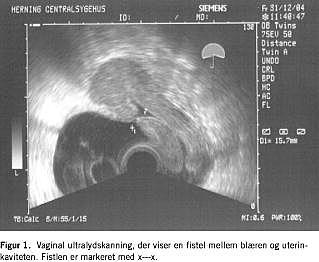

Patienten fik foretaget elektivt sectio to uger før termin på grund af et tidligere kompliceret graviditetsforløb, der endte med sectio i gestationsuge 26. Indgrebet var ukompliceret bortset fra et par dage varende hæmaturi. I efterforløbet blev patienten henvist til sygehuset på mistanke om appendicitis, som dog blev afkræftet. Efter tre uger kontaktede hun egen læge på grund af ufrivillig vandladning, der i første omgang tolkedes som stressinkontinens. To måneder post partum blev patienten atter indlagt med mavesmerter, og under denne indlæggelse fandt man urinafgang gennem vagina. Den tentative diagnose var en vesikovaginal fistel, hvorfor der blev anlagt kateter à demeure. Da kateteret overraskende displaceredes til uterus, blev diagnosen revideret til en vesikouterin fistel, som i øvrigt kunne synliggøres ved en vaginal ultralydskanning (Figur 1). Fistlen blev lukket operativt. I efterforløbet blev patienten kortvarigt behandlet med antibiotika, da der var mistanke om infektion i den interne cikatrice.

Summary We report a case of a vesicouterine fistula occurring after a Caesarean section. There was a noticeable delay in recognizing the fistula, which was, however, clearly visible on a vaginal ultrasound scanning. When urinary incontinence is developed after gynaecologic or obstetric surgery, a fistula must be suspected.